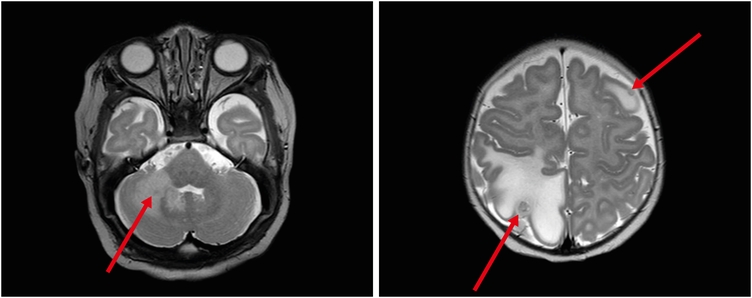

Laboratory evaluations, including a complete blood count with platelet, hemoglobin, coagulation battery, and D-dimer assessment, and liver function, renal function, serum electrolytes, and thyroid function tests, were within normal limits or negative. Abdominal ultrasonography showed mild left pelviectasis (7 mm). Soft tissue mass ultrasonography showed multiple hypoechoic solid masses with markedly increased vascularity, suggesting hemangiomas (Fig. 2). Whole body magnetic resonance imaging (MRI) showed a numerous enhancing skin, subcutaneous, and muscular lesions throughout the body, and a multiple lobulated enhancing mass with a central non-enhancing portion along the anus and buttock areas and involving the right sided of the anal sphincter. Brain MRI demonstrated multiple variably-sized enhancing lesions in the right cerebellum, right medial temporal lobe, left thalamus, and right parietal lobe, with marked perilesional edema; the largest in the right parietal lobe measured up to 6.5 mm (Fig. 3). Echocardiography showed unremarkable findings. Neurologic and eye examinations revealed no abnormalities. To confirm whether multiple hemangiomas are related to genetic abnormality, we additionally performed chromosomal analysis. The test showed no chromosomal structural abnormalities and was 46, XY, which is normal karyotype.

Fig. 3

Brain magnetic resonance imaging before treatment.